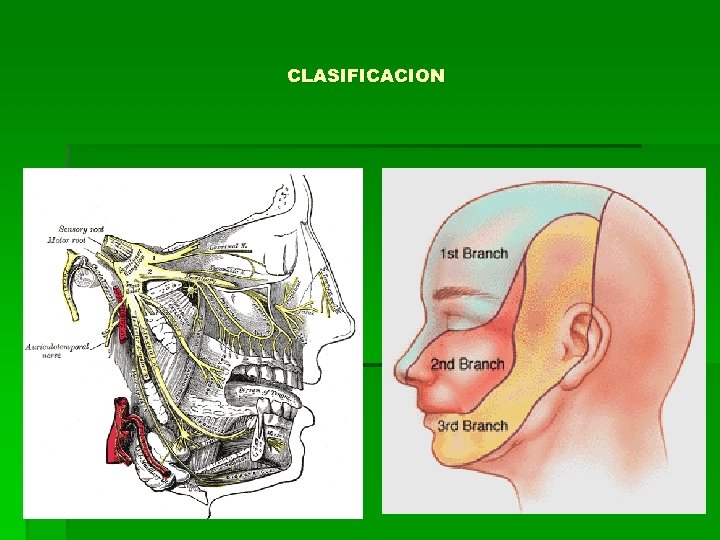

CLASIFICACION

CLASIFICACION